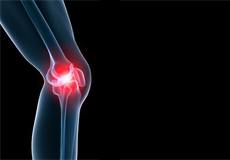

Knee Pain

Knee pain is a common condition affecting individuals of various age groups. It not only affects movement but also impacts your quality of life. An injury or disease of the knee joint or any structure surrounding the knee can result in knee pain.

Knee Osteoarthritis

Osteoarthritis also called degenerative joint disease, is the most common form of arthritis. It occurs most often in older people. This disease affects the tissue covering the ends of bones in a joint (cartilage).In a person with osteoarthritis, the cartilage becomes damaged and worn out causing pain, swelling, stiffness and restricted movement in the affected joint.